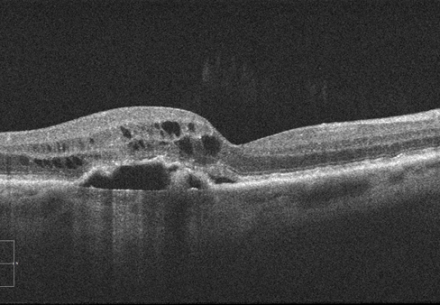

•   SD-OCT: hochauflösende Schichtanalyse der Makula, millimetergenau und wiederholbar

SD-OCT feuchte Makuladegeneration